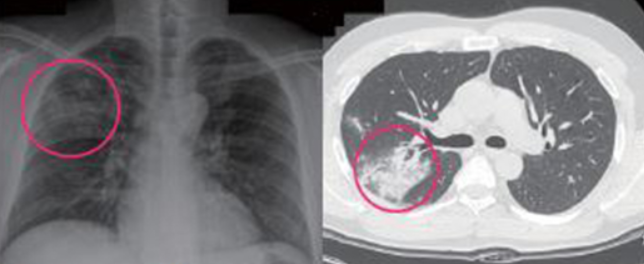

우선 의사의 청진결과로도 대략적 예상이 가능하지만

요즘은 X-ray가 흔한 진단법이기 때문에 X-ray만찍어도 바려 결과를 알 수 있는

장점이 있습니다. 간혹 확인이 어려울 경우 CT도 이어지는 경우가 있습니다.